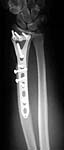

This patient is a 34 yo male raceboat driver who was ejected and had a propeller injury to his left non-dominant arm w/ amputation of digits 2-4 and dorsal wrist laceration and distal radius fracture w/ shaft extension.

We have seen a few of these injuries that are difficult to stabilize w/ standard implants due to the shaft extension. I recently received a Synthes proto-type from Dr. Daniel Rikli in Aurau, Switzerland of the standard T-plate w/long proximal extension. It is a good implant for these unusual injuries. I wanted to get opinions on what others would do w/ standard implants. The plate takes 3.5 mm screws proximally and 3.5 or 2.7 screws distally. In a closed injury I imagine I would use the plate volarly, but due to the dorsal wound and lack of extensor tendons we plated the fx dorsally. I think we all should encourage Synthes to make these plates widely available.